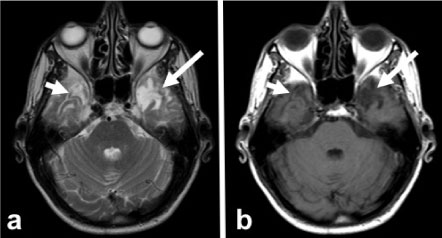

Figure 1: MRI examination performed at the first visit of the patient. Axial T2A image shows (a) heterogeneous signal increase and edema in the left temporal lobe with the 'Swedish cheese' appearance. In the post-contrast axial T1W image (b), heterogeneous contrast enhancement was observed in this region, but perfusion MRI showed low perfusion in rCBF map (c). The very apparent lactate peak observed in MR spectroscopy obtained at the mid TE supports the diagnosis of radiation necrosis. View Figure 1

Figure 2: First year control MRI. Axial T2A image (a) in the left temporal lobe edema decreases, gliosis is observed to develop (arrow). In addition, another T2 hyperintense lesion with a similar character is present in the right temporal lobe (short arrow). Post-contrast axial T1W image (b) shows no contrast enhancement in the left temporal lobe (arrow) and heterogeneous enhancement in the right temporal lobe (short arrow). View Figure 2